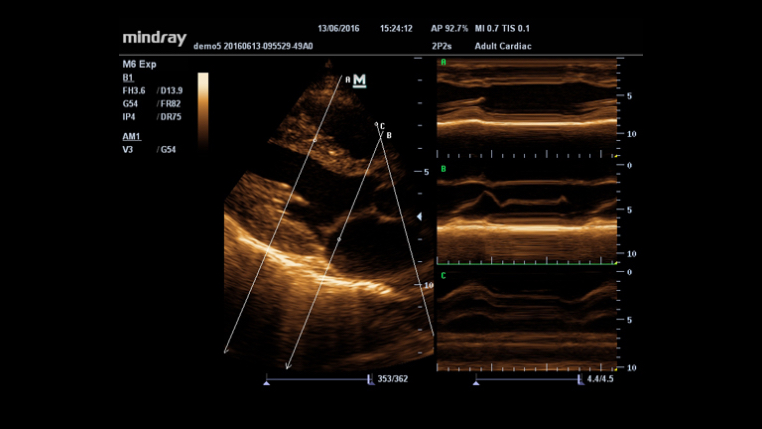

Maximum 8 times tasking for one transmitted beam, resulting in excellent time resolution and higher frame rate.

Permits use of multiple scanned angles to form a single image, resulting in enhanced contrast resolution and improved visualization.